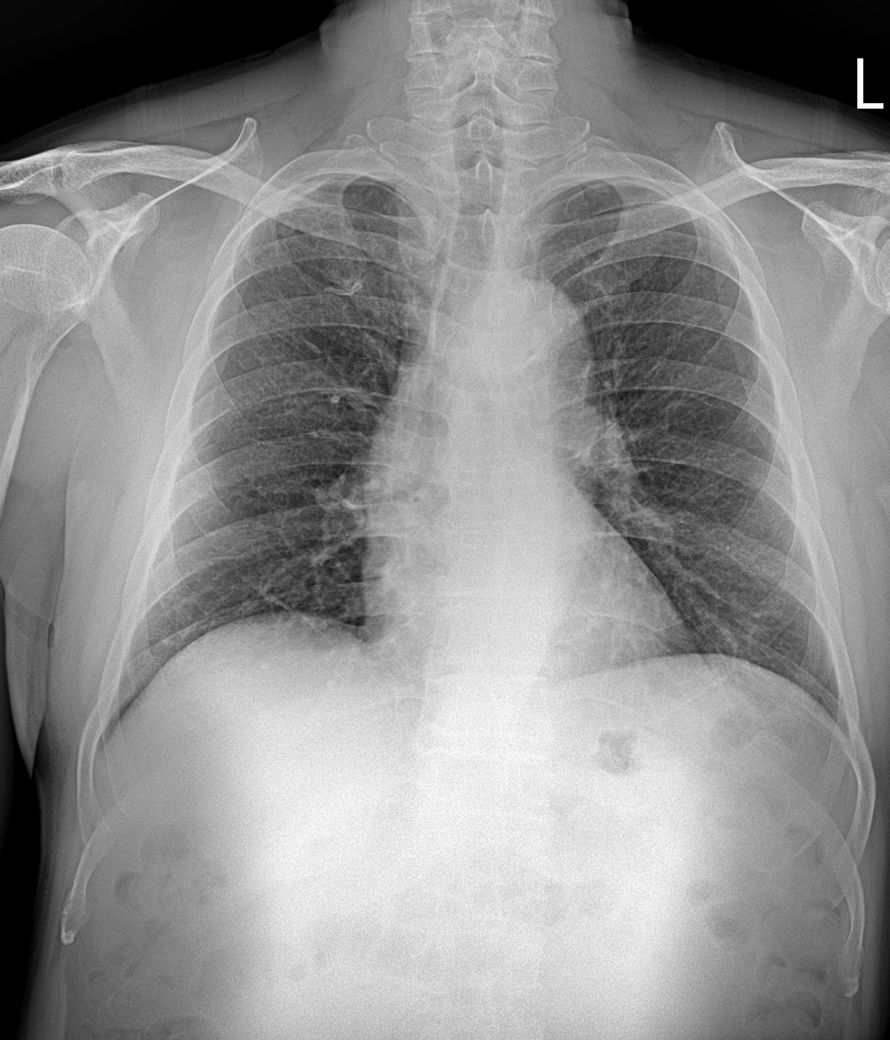

작년 4 월 엑스레이

• 3번 째 사진